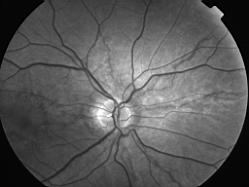

ASSOCIATION STRIES ANGIOIDES ET DYSROPHIE MACULAIRE RETICULEE

NEOVASCULARISATION